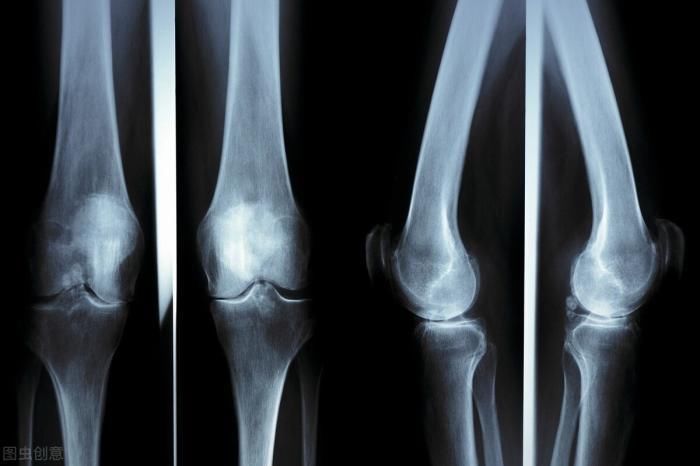

对于孩子而言,决定身高的主要因素是遗传、后期的饮食和生活习惯。我们不得不承认遗传和孩子的身高有一定的关系,但国内一组数据统计普通家庭的孩子身高一般要比富裕家庭的孩子高五到八公分左右。这样也说明了后期的饮食和生活习惯才是孩子身高的决定性因素,所以家长们要正确把握孩子发育的规律,不光是每个年龄阶段发育状况不同,每年中有一段时间内孩子的个头会长得特别快。立冬之后正是孩子的转骨期,也是一年中发育最快的时候,所以家长们要及时观察孩子身体的一些异常,如果出现了转骨期的一些信号就要及时供给营养,好让孩子快速发育。

孩子在转骨期骨骼生长较快,会出现腿抽筋的情况,这是因为破骨细胞的分裂肌肉跟不上骨骼的发育,这个时候家长要及时给孩子吃一些高蛋白钙质含量高的食物,从而促进肌肉的正常发育。